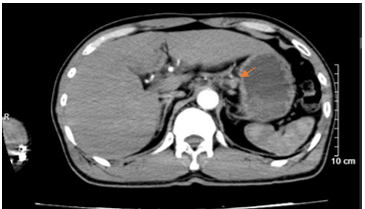

- CTscanner bụng: Dày thành hang vị dạ dày, dày không đều, mất cấu trúc lớp bề dày khoảng 18mm, trên đoạn dày khoảng 75mm, sau tiêm ngấm thuốc, không thấy thâm nhiễm, cạnh bờ cong lớn và bờ cong nhỏ lân cận có vài hạch (>5 hạch), hạch lớn nhất kích thước 16 x 10mm, sau tiêm ngấm thuốc.

Hình 3. Hình ảnh chụp cắt lớp vi tính ổ bụng. Hình ảnh các hạch cạnh bờ cong nhỏ dạ dày, sau tiêm ngấm thuốc, hạch lớn nhất kích thước 16 x 10mm (mũi tên màu cam)